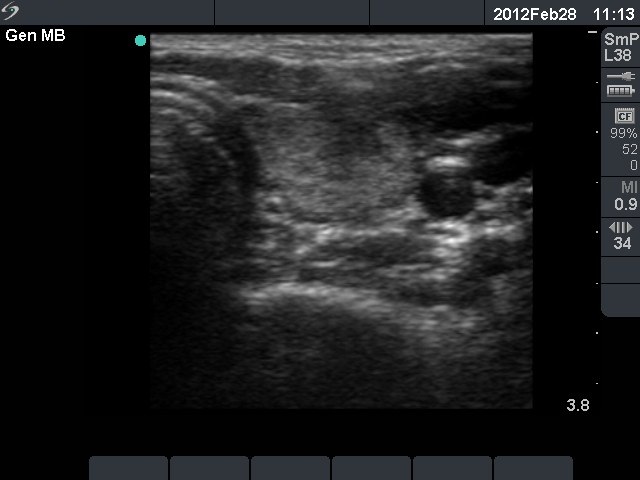

Initial investigation 5 months after delivery (1st and 2nd rows of images)

Ultrasonography: the thyroids were echonormal. The echogenicity index was around 15%. There was no nodule. The vascularization was average.Cytology resulted in Hashimoto's thyroiditis.